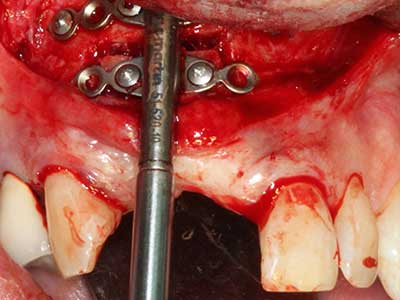

Quando le procedure chirurgiche vengono eseguite sull'osso nelle immediate vicinanze di strutture sensibili, come vasi sanguigni o nervi, gli strumenti rotanti pongono un rischio significativo di lesione iatrogena. I dispositivi piezoelettrici possono essere utili per la preparazione delle coperture ossee e la rimozione del tessuto duro in prossimità dei nervi, in particolare per la loro esposizione dopo una lesione iatrogena, ma anche durante la lateralizzazione dei nervi per le procedure di resezione e ricostruzione o il posizionamento di impianti (figg. 17-20). Il contatto leggero tra puntina piezoelettrica e nervo non causa generalmente danni, ma se si procede senza prestare attenzione con movimenti a sega o raccordi con residui di substrati ossei possono verificarsi danni al nervo temporanei o anche permanenti. Il rischio di danno, tuttavia, è considerato sostanzialmente inferiore al rischio presente utilizzando seghe o frese (Pereira, Gealh et al. 2014).

Indicazione: terapia parodontale